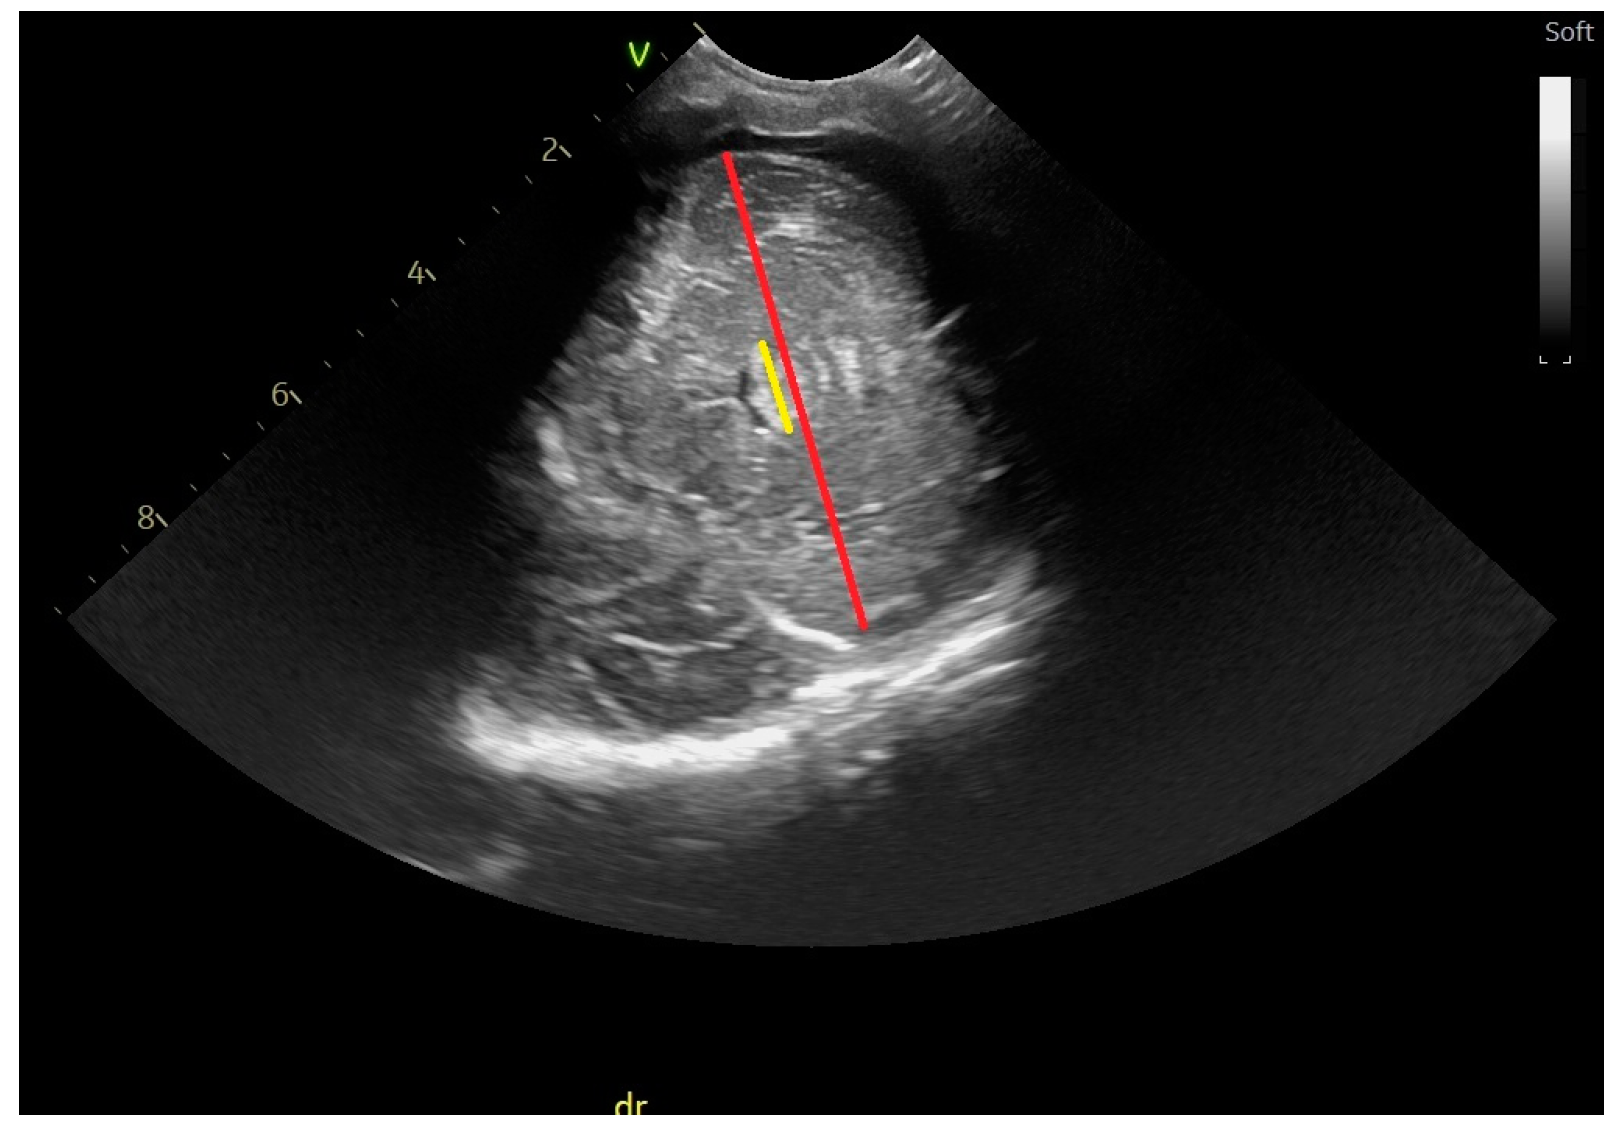

2.2. Head Ultrasound Measurements at TEA